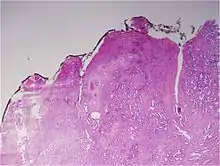

Most often, a urologist or radiologist will remove a cylindrical sample (biopsy) of prostate tissue through the rectum (or, sometimes the perineum), using hollow needles, and biomedical scientists in a histology laboratory prepare microscope slides for H&E staining and immunohistochemistry for diagnosis by a pathologist. If the prostate is surgically removed, a pathologist will slice the prostate for a final examination.